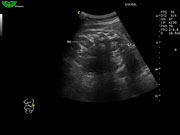

Алгоритм снижения зернистости изображения (SPA)

- Программный расчет в реальном времени.

- Позволяет различать малейшие различия в тканях.

- Удаляет шум и делает нечеткие края более различимыми.

- Удаляет шум и делает изображение более похожим на анатомические стандарты.

Многократное составное отображение (MCI)

Как в бестеневой лампе, ультразвуковая волна передается под разными углами для предоставления врачу большего количества информации и получения более качественных изображений.

В этом специальном режиме сканирования B датчик передает звуковые волны не только перпендикулярно, а также и в других плоскостях, вращая направление распространения волн. Затем эти плоскости перекрываются и формируют конечное изображение. Это улучшает пространственное и контрастное разрешение и уменьшает отражения на границе.